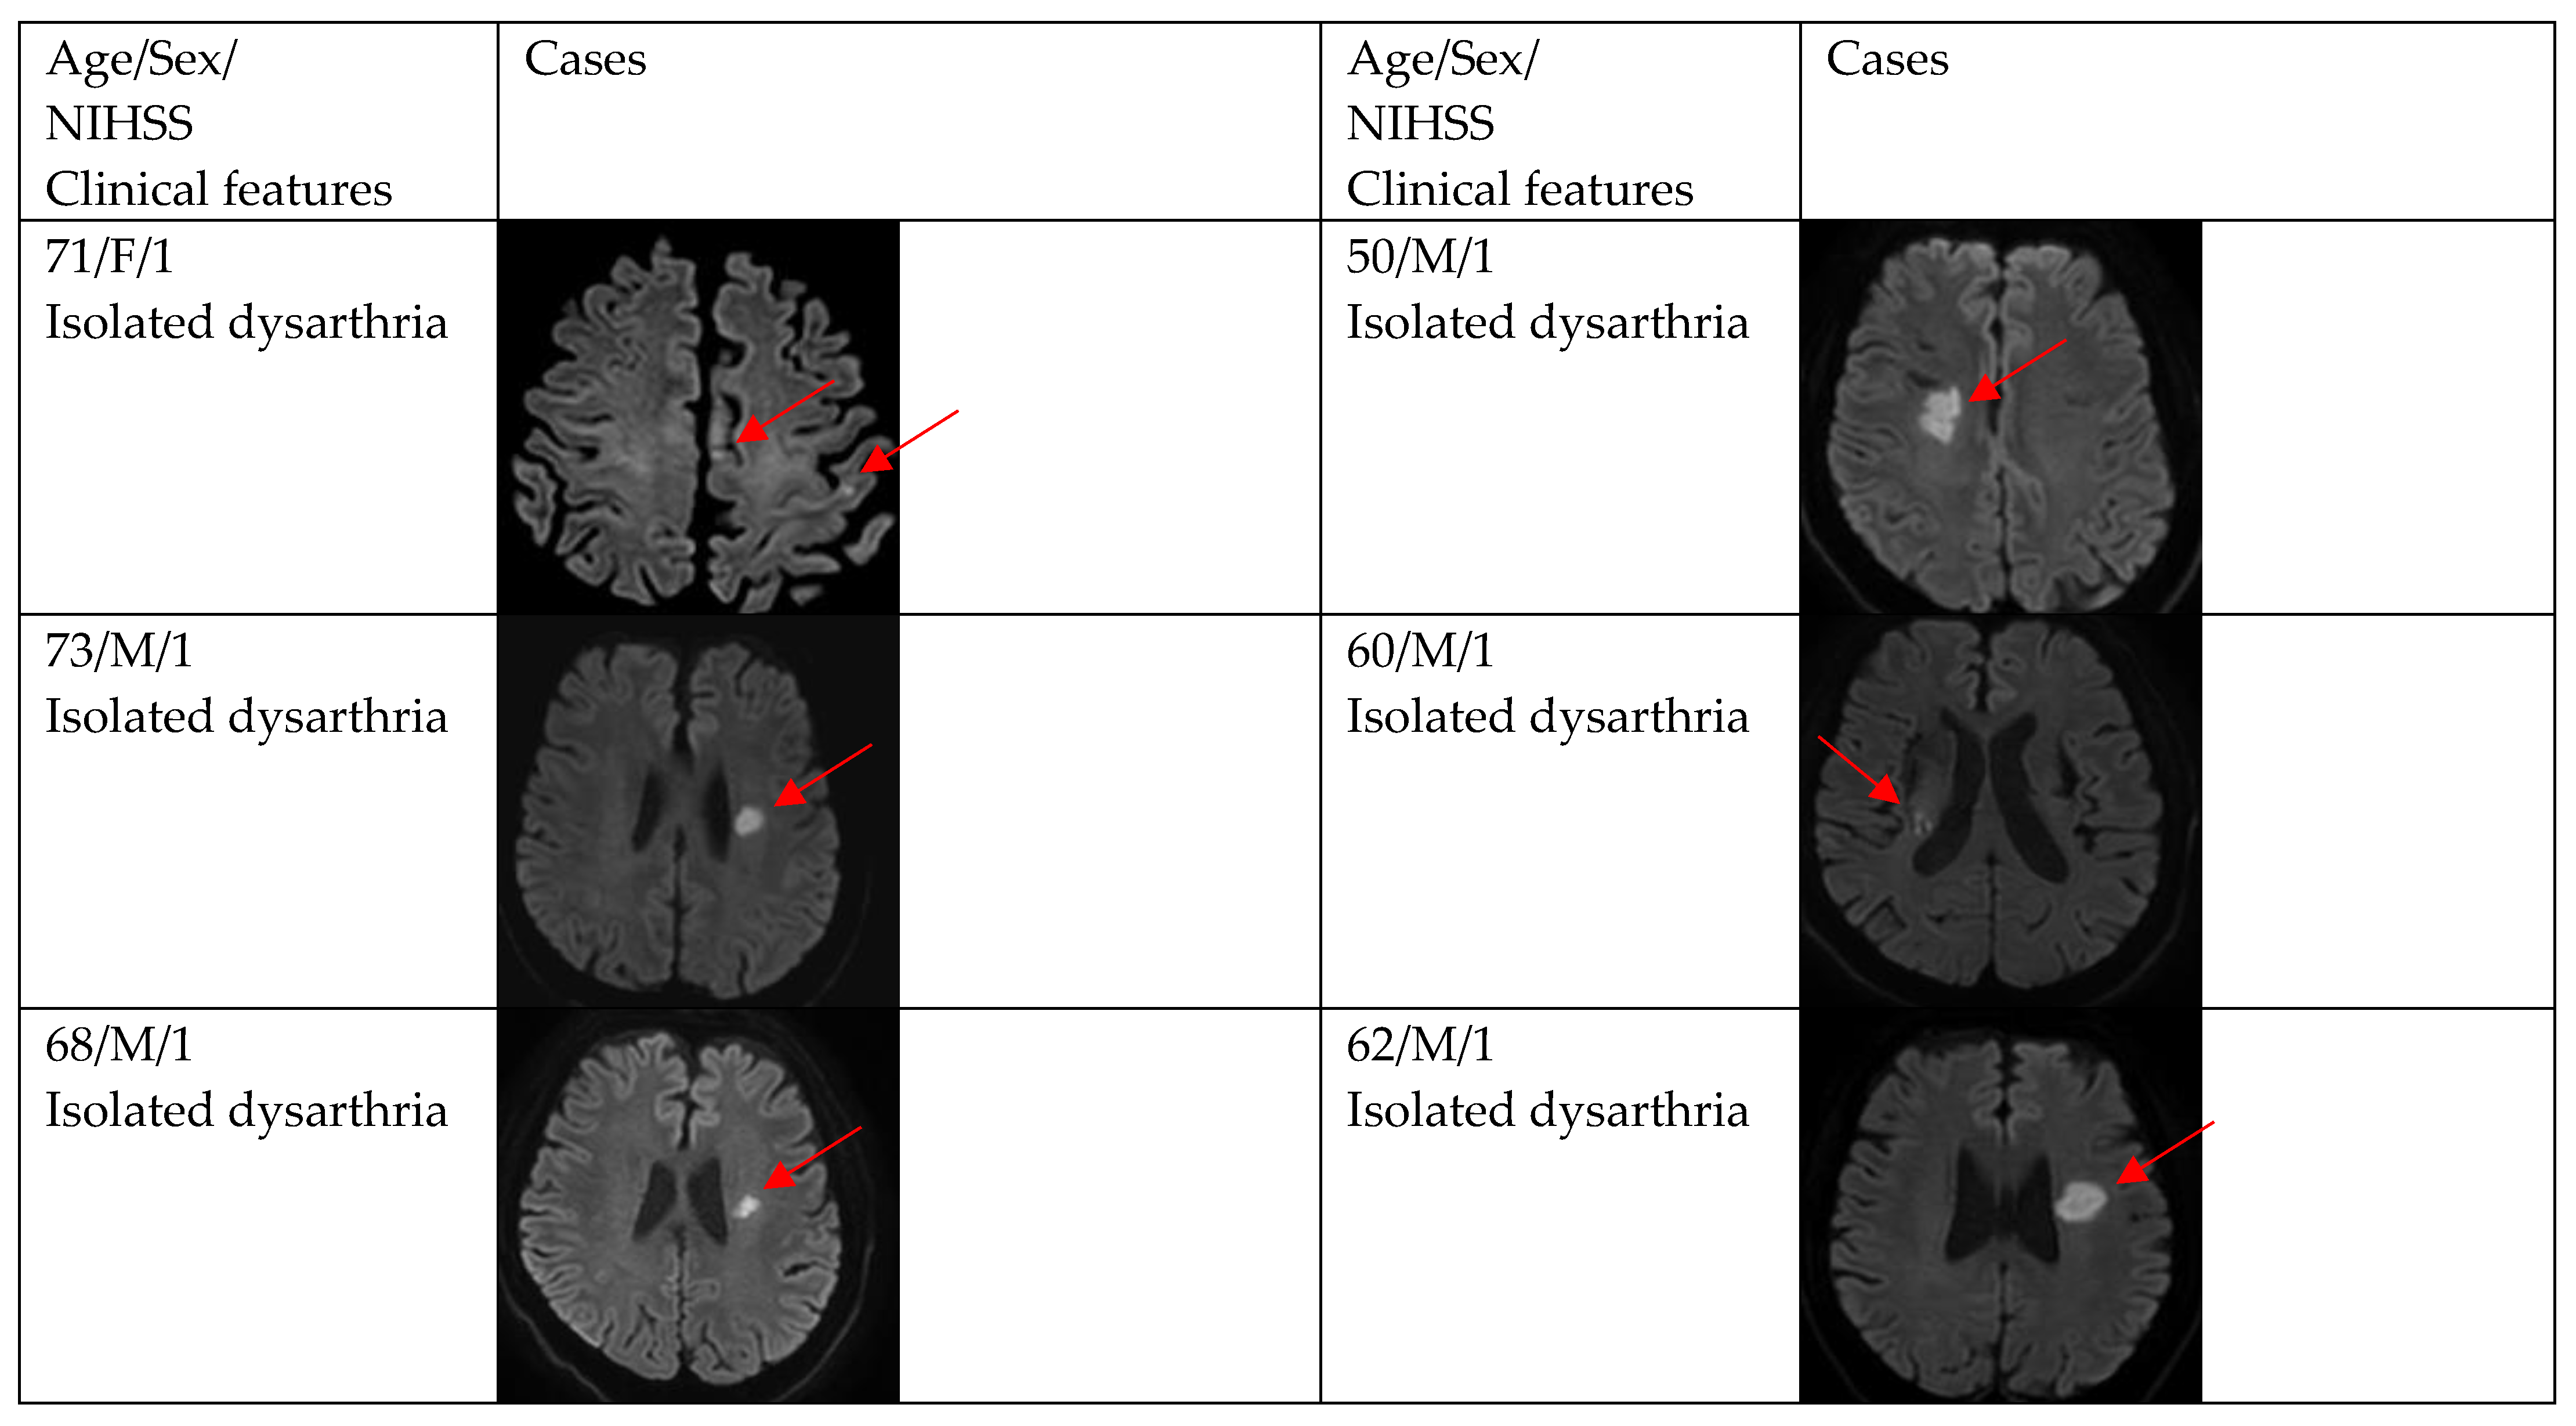

3. Results

| DWI positivity | 12 (66.7) | 29 (87.9) | 0.154 |

| Single and small lesion | 10 (83.3) | 16 (55.2) | |

| Multiple or territorial lesions | 2 (16.7) | 13 (44.8) | |